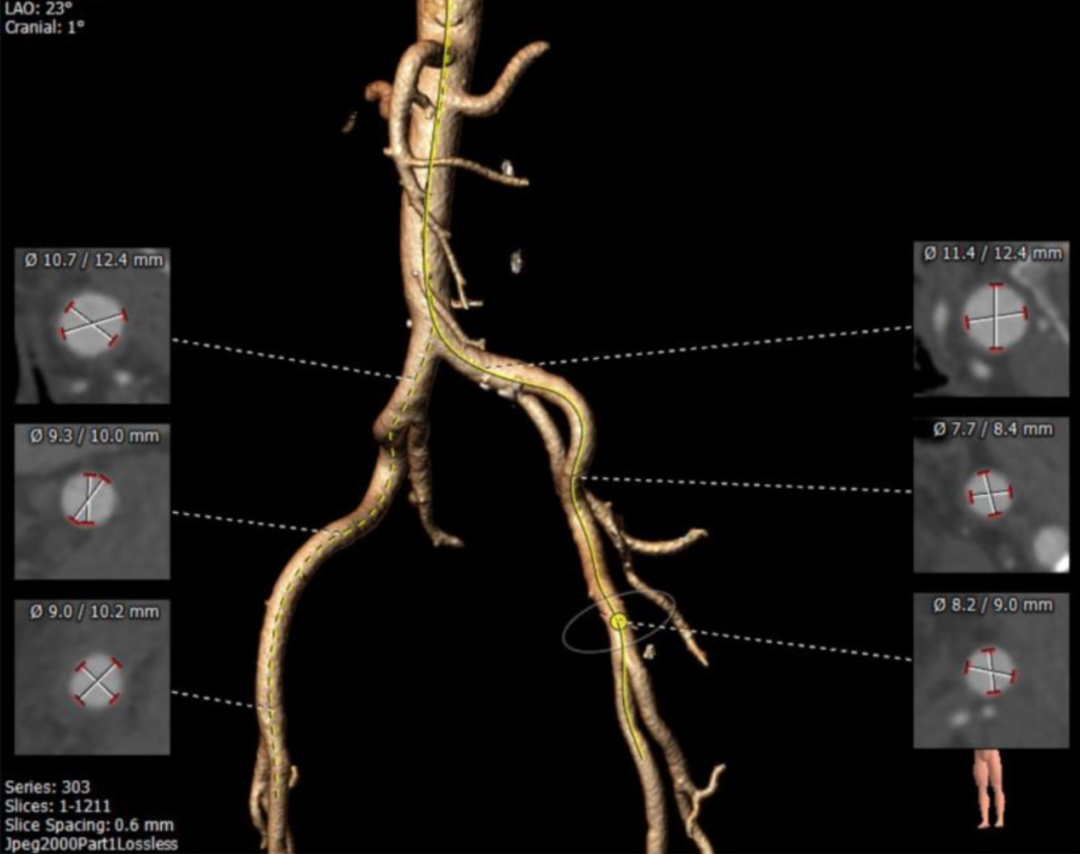

主动脉根部解剖

三叶式主动脉瓣,轻度钙化,钙化分布均匀,多位于瓣叶附着缘处血管内壁。主动脉瓣瓣环周长80.9mm,平均周长径25.7mm。瓦氏窦内径可。

左冠开口高度17.9mm,右冠高度19.5mm,冠状动脉散在钙化。

瓣环上及主动脉解剖

血管入路解剖

外周入路血管散在钙化,双侧髂外动脉管径处于临界范围

经过团队严谨的评估及充分的讨论,使用右侧股动脉为主入路,左侧辅助入路。推荐跨瓣角度为LAO21°,CAU5左右。瓣叶略有增厚,未见明显融合嵴,预估无需球囊扩张。预装载TaurusOne®AV29瓣膜。推荐释放角度LAO 21°,CAU 8°(右窦中心位),植入深度标准位(瓣环下2-4mm)。